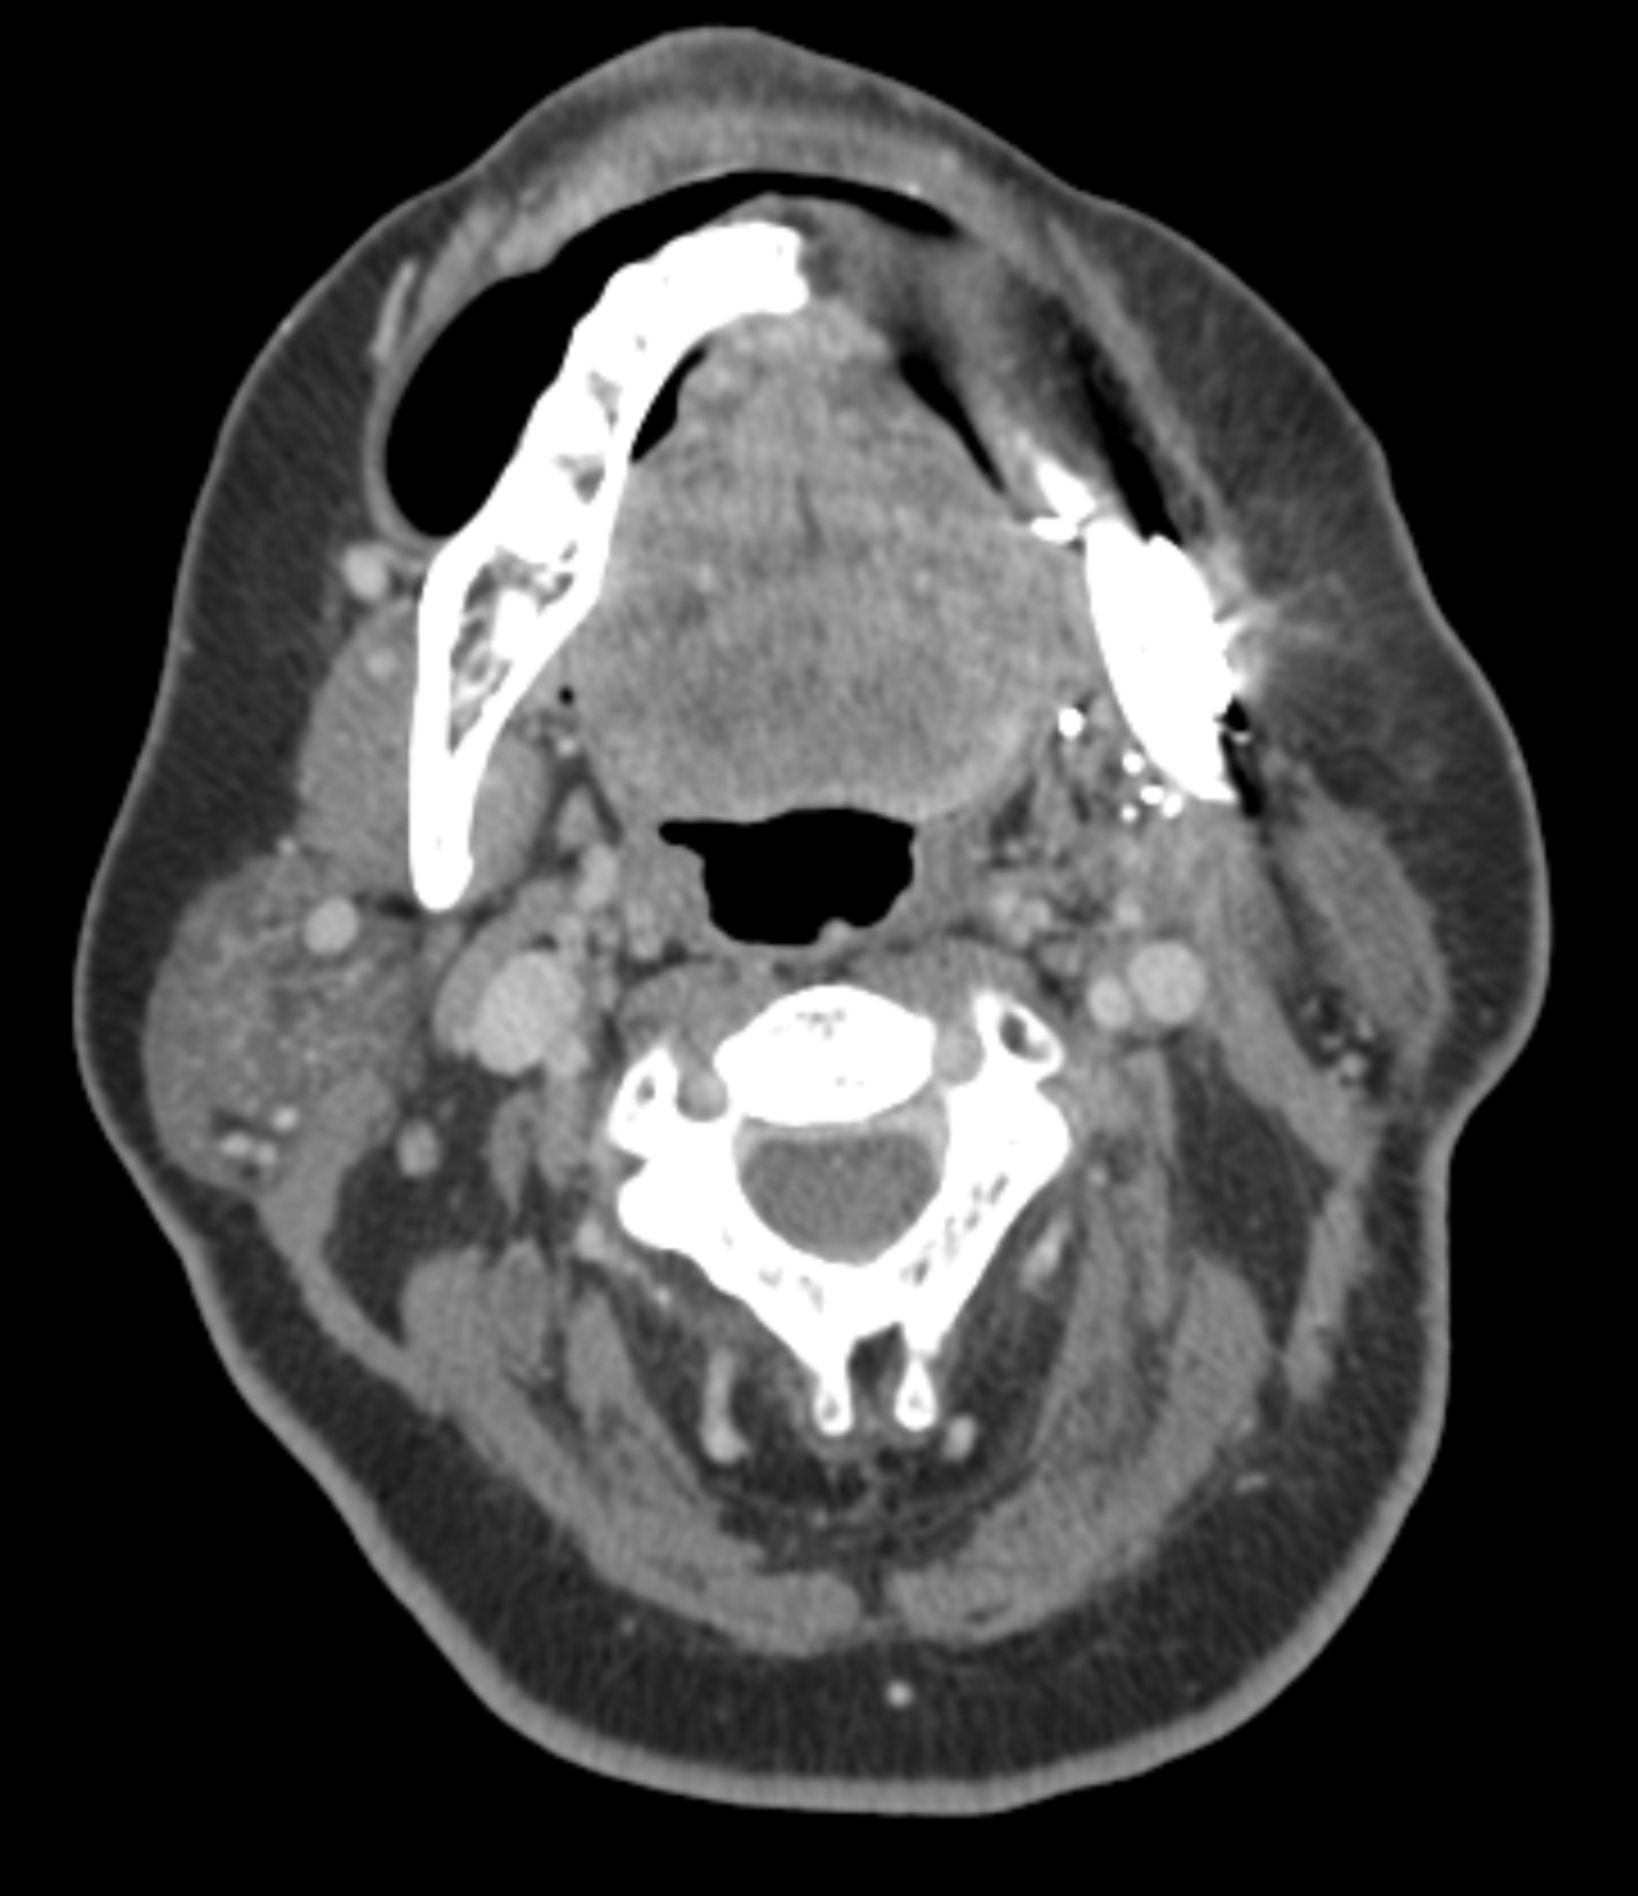

CT Scan

A computed tomography scan makes use of computer-processed combinations of many X-ray measurements taken from different angles to produce cross-sectional images of specific areas of a scanned object, allowing the user to see inside the object without cutting.

Well, we promised you an update in mid November and we thought it would be the last one. Unfortunately a lot has happened since our trip to UK, visiting parents, kids and grandkids. Sadly, the cancer has returned as a big lump on the left jaw line, close to the original surgery site.

After a series of consultations, CT and PET scans, the plan of attack is to have a series of seven immunotherapy infusions three weeks apart, starting on 17th December, another extensive surgery on 27th December to remove the tumor, and radiation treatment once I have recovered from the surgery.